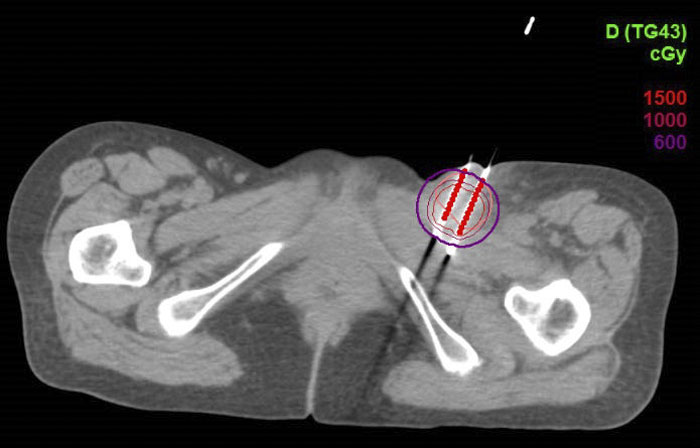

CT引导下的左侧腹股沟淋巴结组织间插植剂量图

该患者的淋巴结转移病灶在浅表,外照射剂量无法达到根治效果,且易出现皮肤破溃等放射损伤。选择CT引导下无痛组织间插植近距离放疗,可实时调整金属针的进入方向和位置,针对肿瘤给予更适形、更精准的放射治疗,在根治肿瘤的同时有效减少了周围正常组织的放射损伤。

CT影像引导下的三维插植近距离放疗,可通过三维视角来进行施源器的植入与固定,定位更精确,该治疗已广泛应用于宫颈癌、子宫内膜癌等妇科恶性肿瘤患者。根据靶区的不同,可以个体化植入施源器,更准确地定位肿瘤组织的位置,通过非共面多角度进针,使肿瘤放疗靶体积达到处方剂量要求,在给予高剂量照射的同时,保证肿瘤周围正常组织受到照射的剂量控制在可接受范围内,从而提高患者的治疗效果和安全性,为晚期难治性妇科恶性肿瘤患者提供了新的治疗希望。